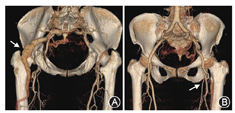

患者女,69岁,因"发现左臀部搏动性肿块1年"住院治疗,自诉有数年活动后下肢不适症状。查体:左臀部扪及搏动性包块,大小约5 cm×5 cm,轻压痛,左侧股动脉搏动弱,腘动脉搏动尚可,足背动脉未及,右侧正常。下肢CT血管造影(CTA)见髂内动脉发出粗大分支至左下肢,伴瘤样扩张,同侧股动脉纤细(图1)。术前诊断为永存坐骨动脉合并坐骨动脉瘤形成。于局麻下行下肢动脉造影,测量瘤体长度95 mm,近端直径13 mm,远端直径11 mm(图2A),遂选用戈尔公司viabahn支架13 mm×13 mm×100 mm一枚及美敦力公司Endurant支架16 mm×16 mm×93 mm一枚,支架重叠约5 cm,术后瘤体不显影,无内漏(图2B)。术后左臀部搏动性肿物消失,疼痛症状明显好转。术后随访至29个月,CTA复查支架无狭窄、无变形,下肢血流通畅(图3A)。后患者自行停用抗血小板药物,随访至术后46个月,支架完全闭塞(图3B),但患者未诉下肢缺血症状,决定继续随访观察。

注:A图:箭头所示为扭曲的坐骨动脉瘤;B图:箭头所示为发育不良的股浅动脉